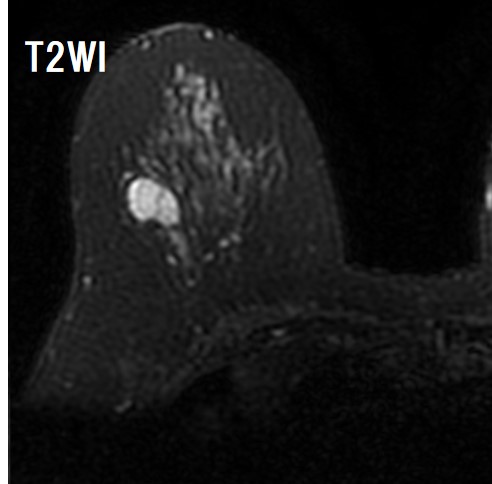

Dark internal septationがある

背側に分葉状の部分がある